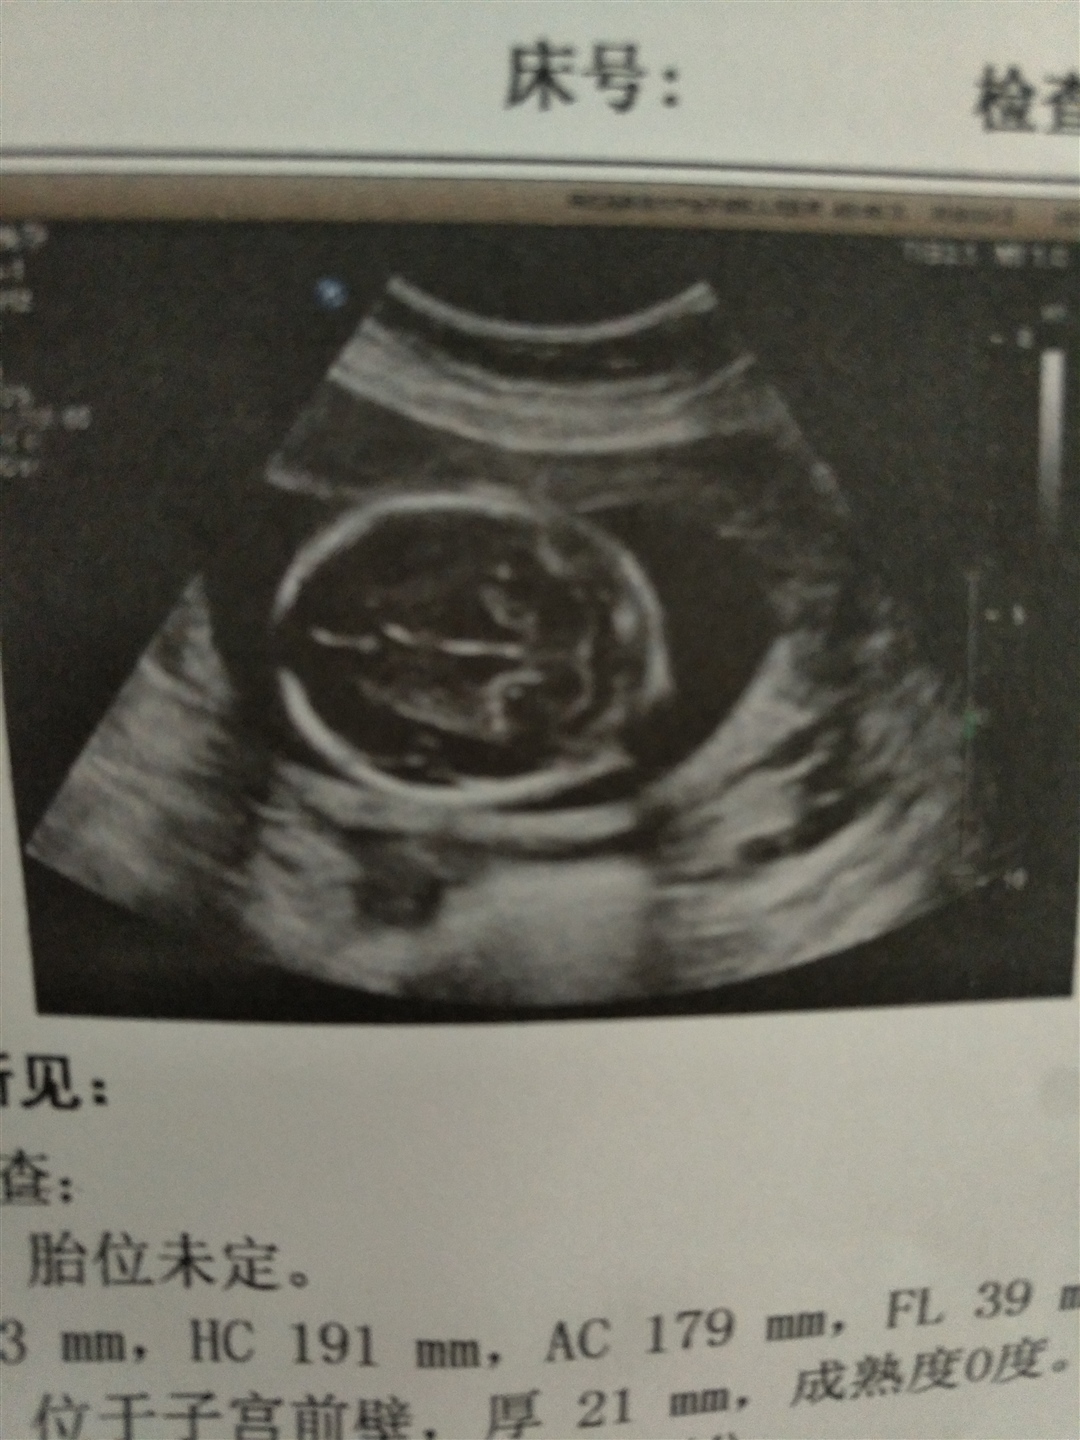

胎位不正,脚朝下!

孕26周+3天